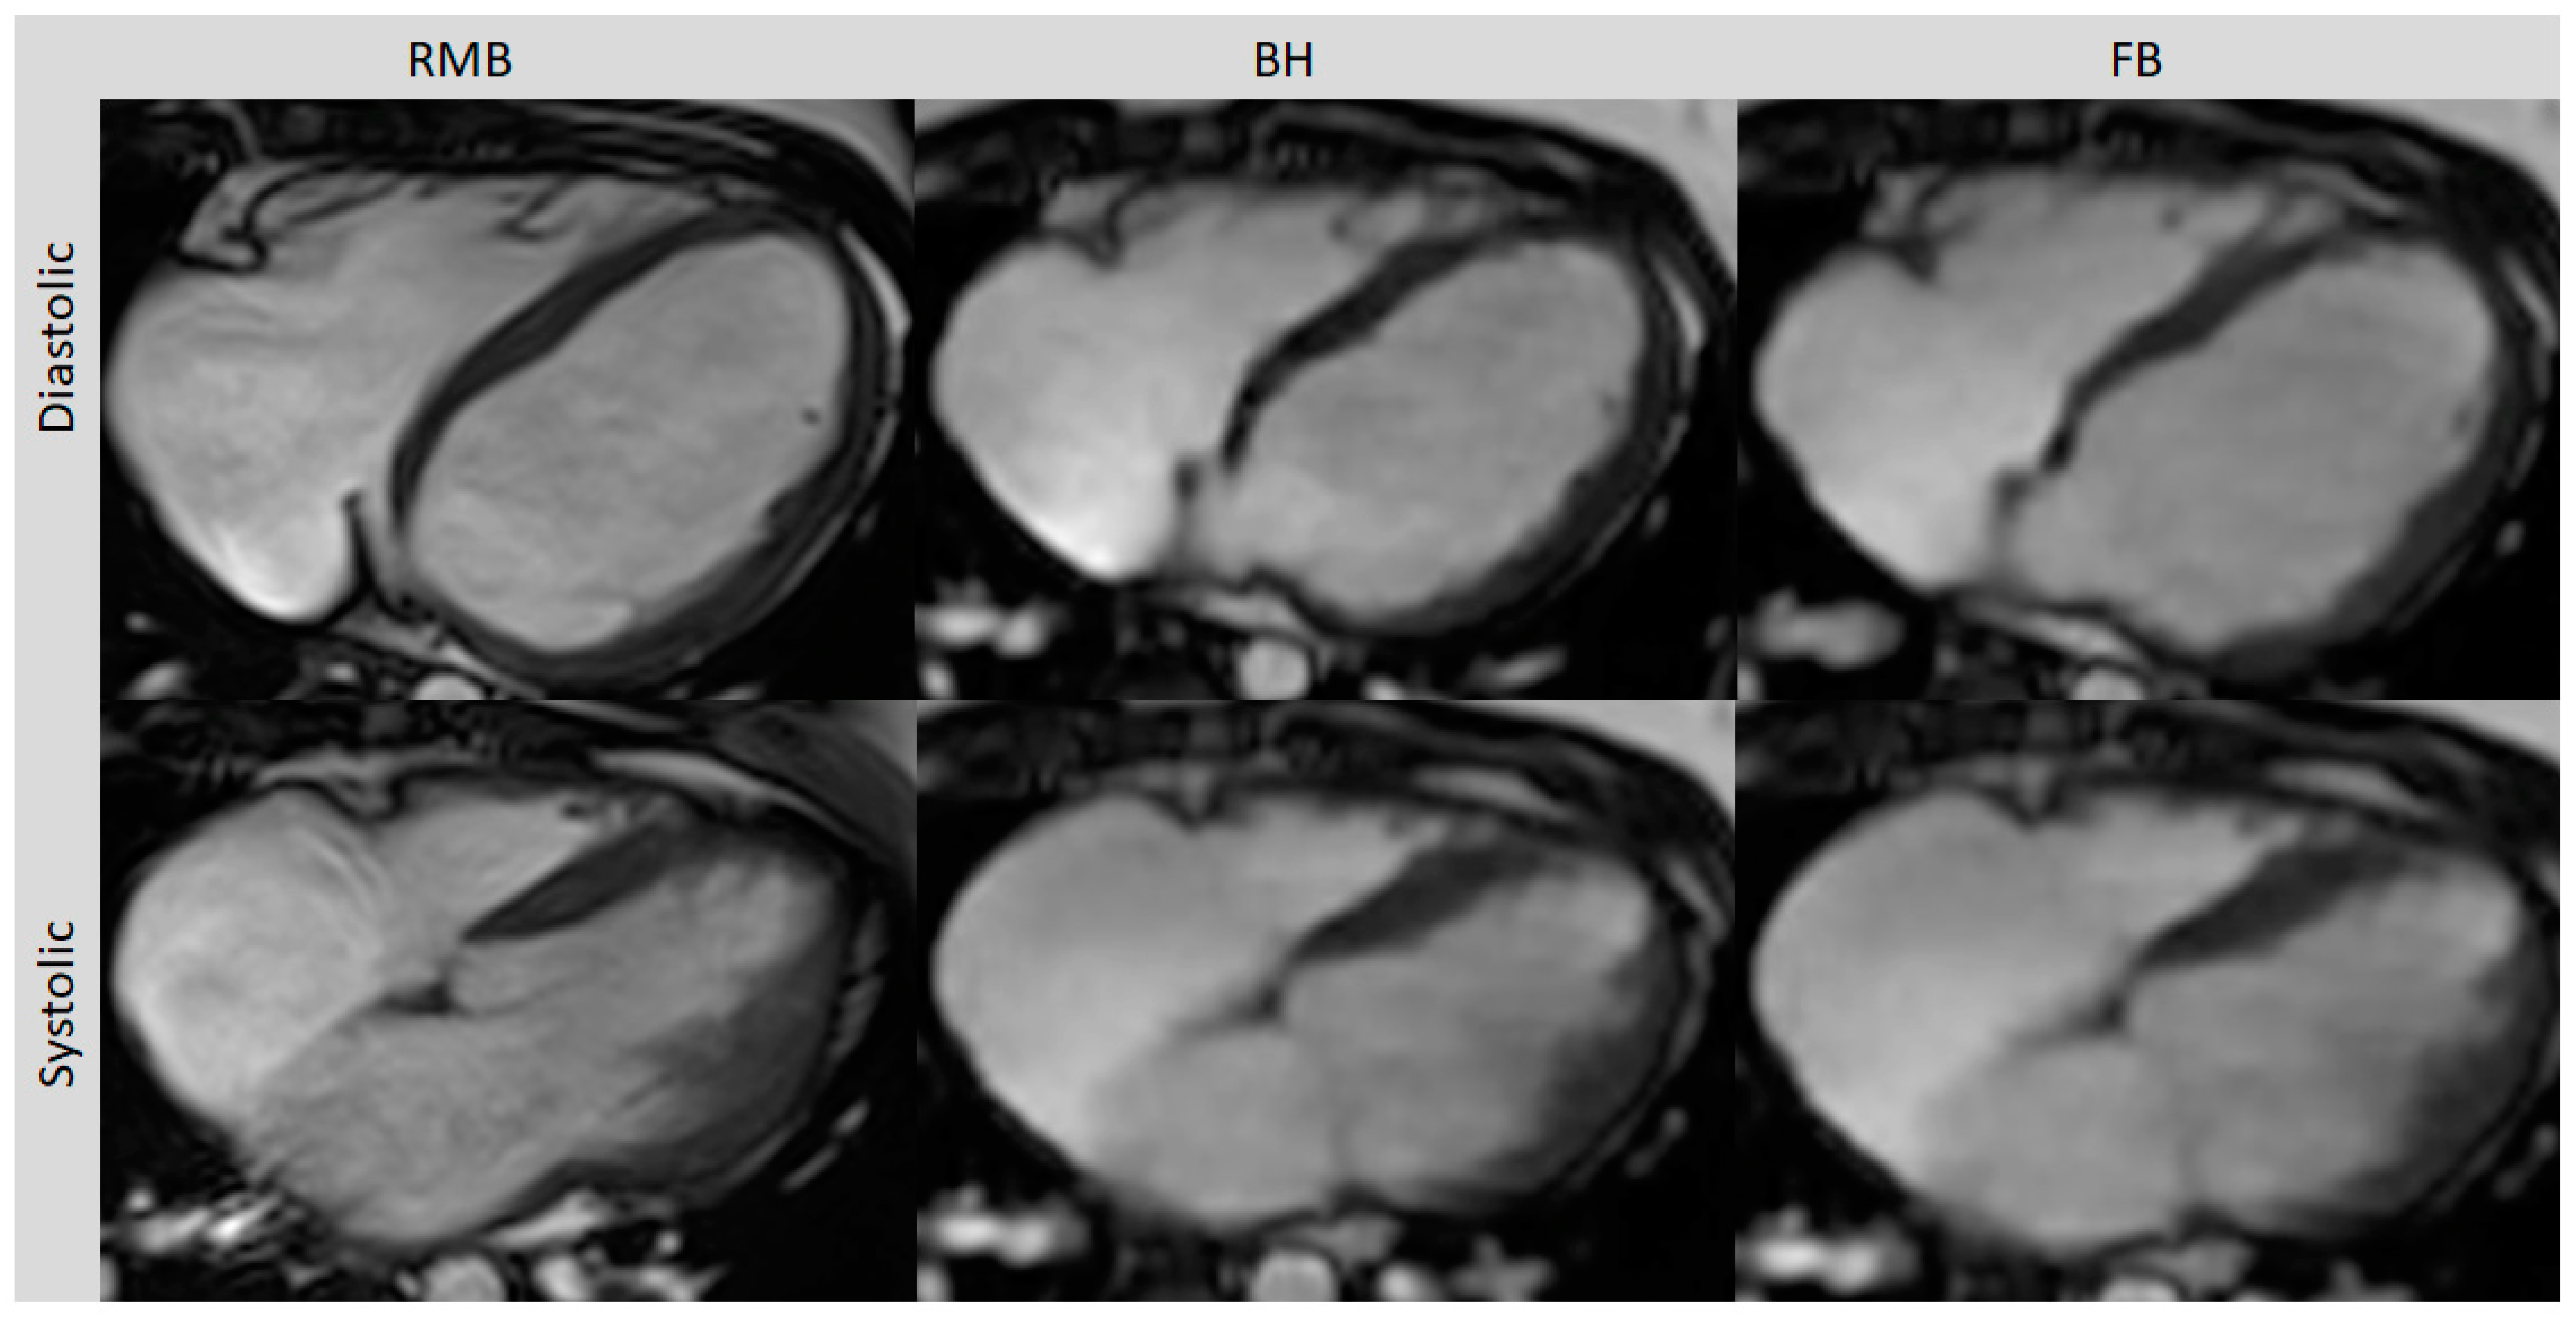

Figure 1.

Axial slices of all three cine sequences in systolic and diastolic phases. FB and BH images are almost equivalent to RMB in the delineating blood–myocardium boundary but with typically a slightly blurrier aspect. Retrospective segmented multi-breath hold (RMB), real-time single/double breath hold (BH), real-time free breathing (FB).

Comparing all three methods, the best image quality was provided by RMB (4.5; range 2 to 5) compared to BH (3.9; range 3 to 5; p = 0.04) and FB (3.6; range 3 to 5; p < 0.01). The image quality with BH was slightly better than with FB but the difference did not reach statistical significance (p = 0.07). The diagnostic confidence was comparable between RMB and BH (p = 0.65) and between RMB and FB (p = 0.84). With RMB, 90% of the cases were rated with high, 5% with intermediate, and 5% with low confidence, whereas with CS-BH and CS-FB, 80% and 75% were rated with high confidence, respectively, and 20% and 25% with intermediate confidence, respectively. Poor image quality with RMB was due to artifacts caused by arrhythmia, whereas BH and FB delivered diagnostic-level image quality in this case (Table 2). Representative images from RMB, BH, and FB are shown In Figure 1 and Figure 2.